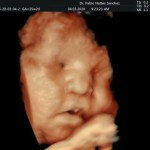

- La anatomía fetal: Diagnostico de Malformaciones Estructurales de aparición tardía (displasias esqueléticas, alteraciones cardíacas pequeñas, alteraciones de la vía urinaria y obstrucciones intestinales).